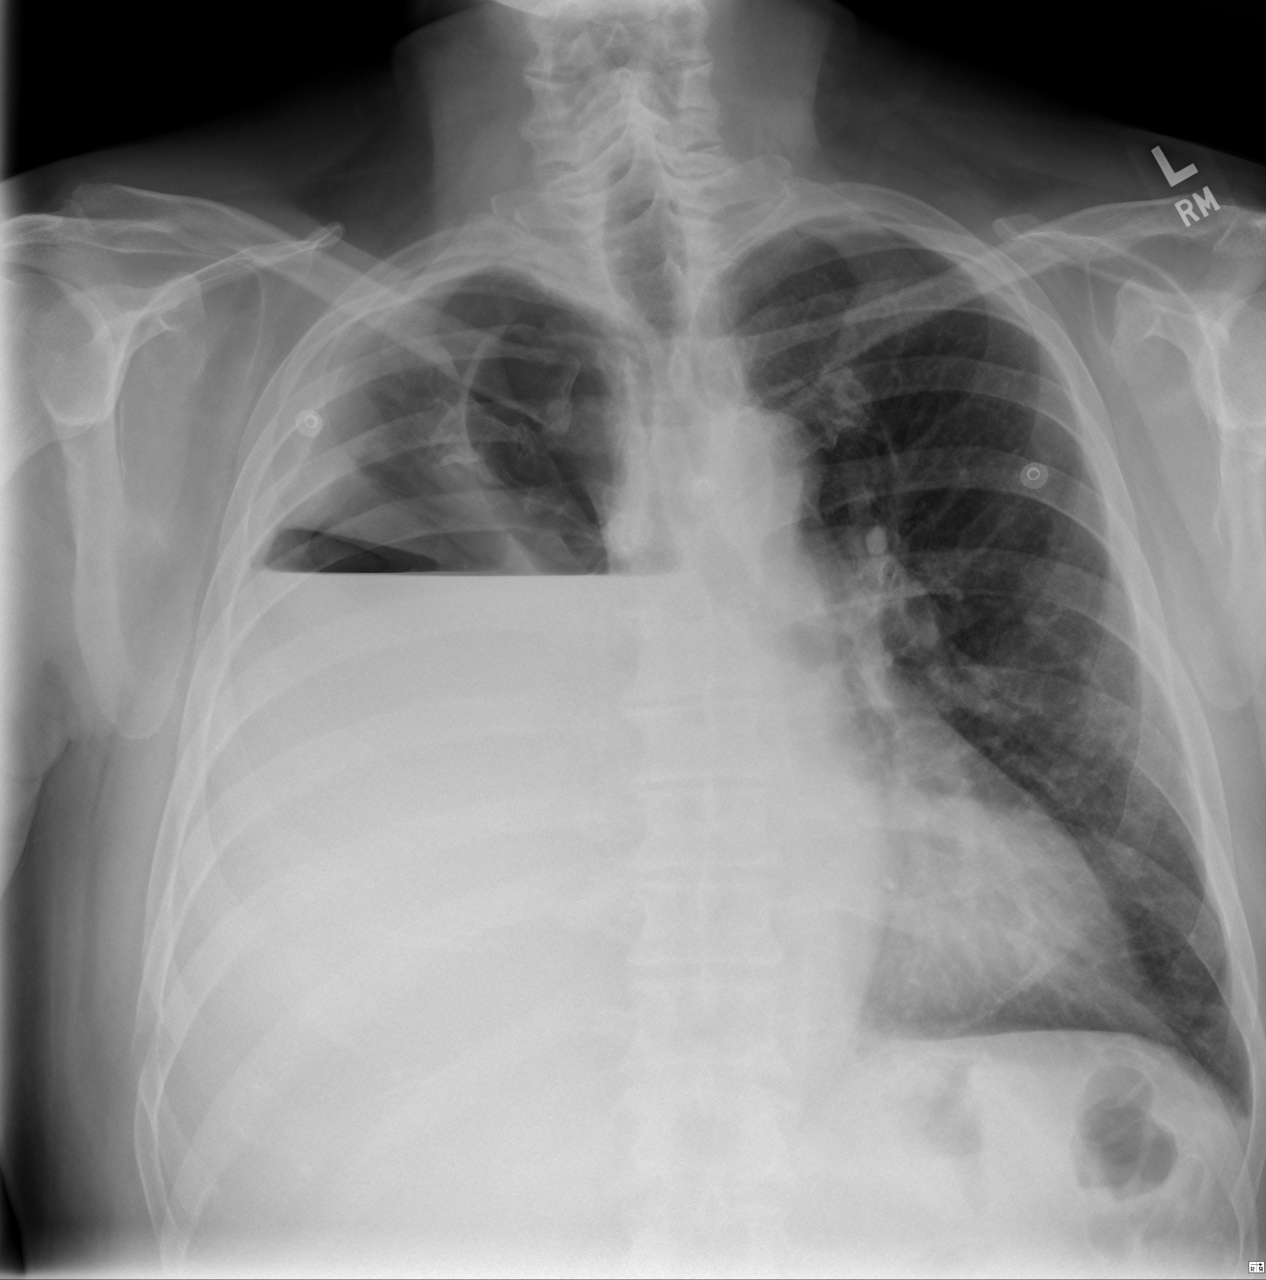

Sur la radio de thorax, le médiastin est repoussé par l’opacité, il est donc comprimé par un épanchement pleural.

Dans le cas d’une atélectasie le médiastin aurait été attiré vers l’opacité.

L’angioscanner thoracique est l’examen de choix pour éliminer une embolie pulmonaire, ici, il permettra de plus d’explorer l’étiologie de la pleurésie.

Vous recevez les images clés du scanner thoracique. Mme F. est hospitalisée. Elle a été bien soulagée par la ponction pleurale. Vous organisez une fibroscopie bronchique qui retrouve un adénocarcinome bronchique TTF1+, envahissant la bronche intermédiaire droite.